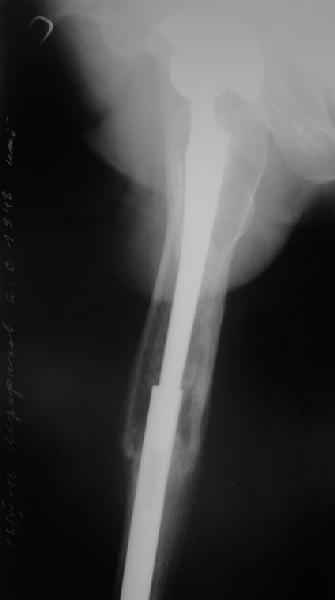

[Ortho] Перипротезный перелом

Пациента удалось осмотреть недавно. Достигнутый результат сохраняется.

Перелом бедра сросся. Конечность опорная и безболезненная, ходит без

трости. Ножка, похоже, реинтегрировалась, как и надеялись.

Снимки и фото в приложении.

Надо ли что-то делать дальше, как полагаете? Убрать винты? Убрать

"удлинитель ножки"? Или оставить все, как есть? Спасибо заранее.